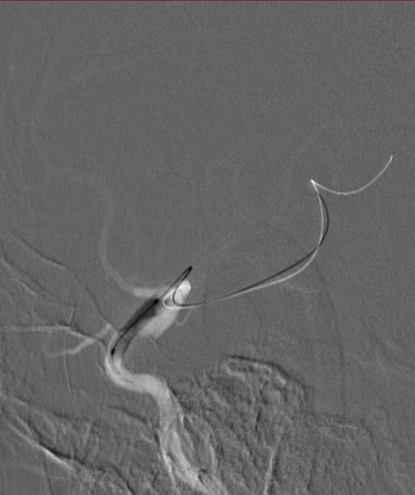

治疗过程

将 6F 导引导管送至 C3 段。

导丝怎么扩【载药时代 球扩天下】NOVA DES®颅内药物洗脱支架在颈内动脉颅内段重度狭窄中的应用体会二例!_https://www.jmylbn.com_新闻资讯_第24张

导引导管到位,导丝通过病变

通过微导丝携带球囊至狭窄段。

导丝怎么扩【载药时代 球扩天下】NOVA DES®颅内药物洗脱支架在颈内动脉颅内段重度狭窄中的应用体会二例!_https://www.jmylbn.com_新闻资讯_第25张

球囊通过病变

球囊到位后准确定位后缓慢扩张球囊。

导丝怎么扩【载药时代 球扩天下】NOVA DES®颅内药物洗脱支架在颈内动脉颅内段重度狭窄中的应用体会二例!_https://www.jmylbn.com_新闻资讯_第26张

球囊扩张过程

扩张后撤出球囊造影,见狭窄有所改善。

导丝怎么扩【载药时代 球扩天下】NOVA DES®颅内药物洗脱支架在颈内动脉颅内段重度狭窄中的应用体会二例!_https://www.jmylbn.com_新闻资讯_第27张

扩张后造影

通过导丝携带球扩支架到达病变位置。

导丝怎么扩【载药时代 球扩天下】NOVA DES®颅内药物洗脱支架在颈内动脉颅内段重度狭窄中的应用体会二例!_https://www.jmylbn.com_新闻资讯_第28张

支架通过病变

缓慢扩充球囊释放支架。

导丝怎么扩【载药时代 球扩天下】NOVA DES®颅内药物洗脱支架在颈内动脉颅内段重度狭窄中的应用体会二例!_https://www.jmylbn.com_新闻资讯_第29张

支架释放